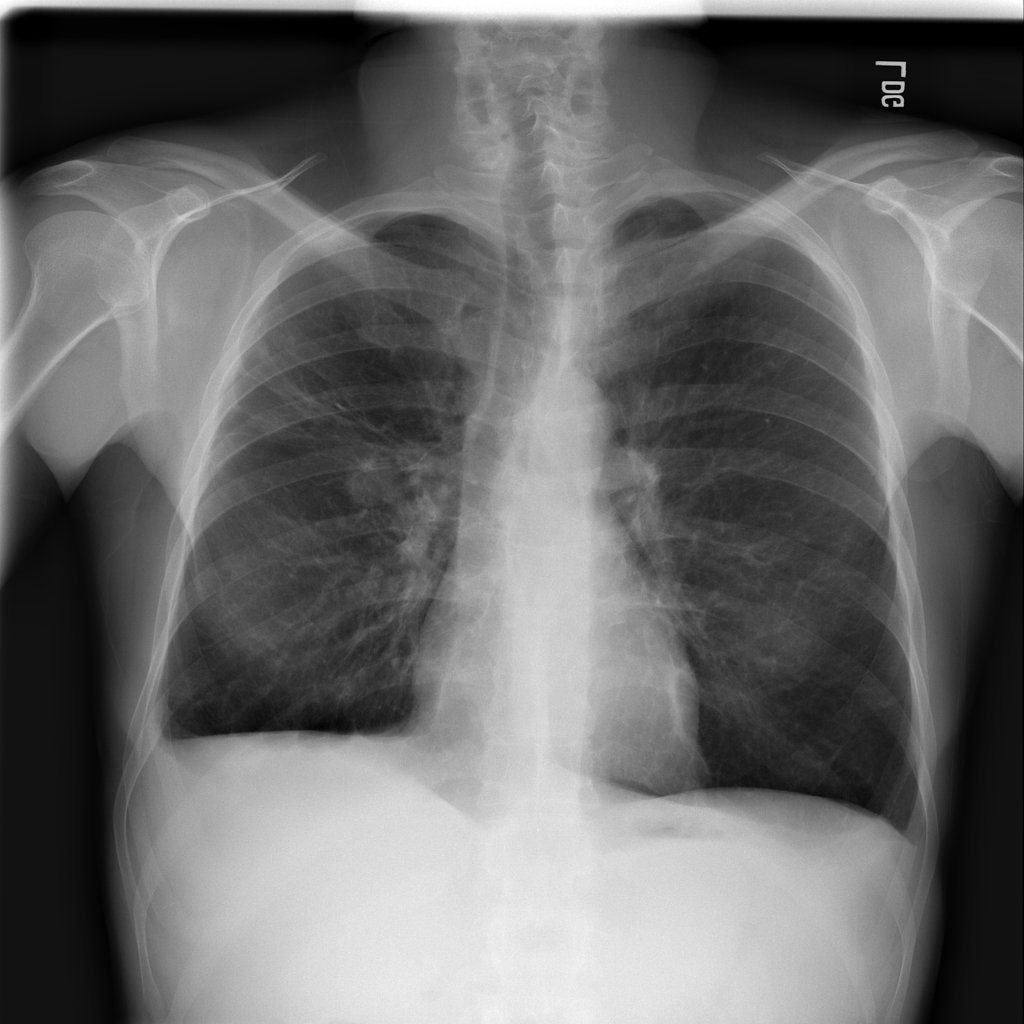

PAT-250B · IMG-000Nodule

PAT-250B · IMG-000

PA